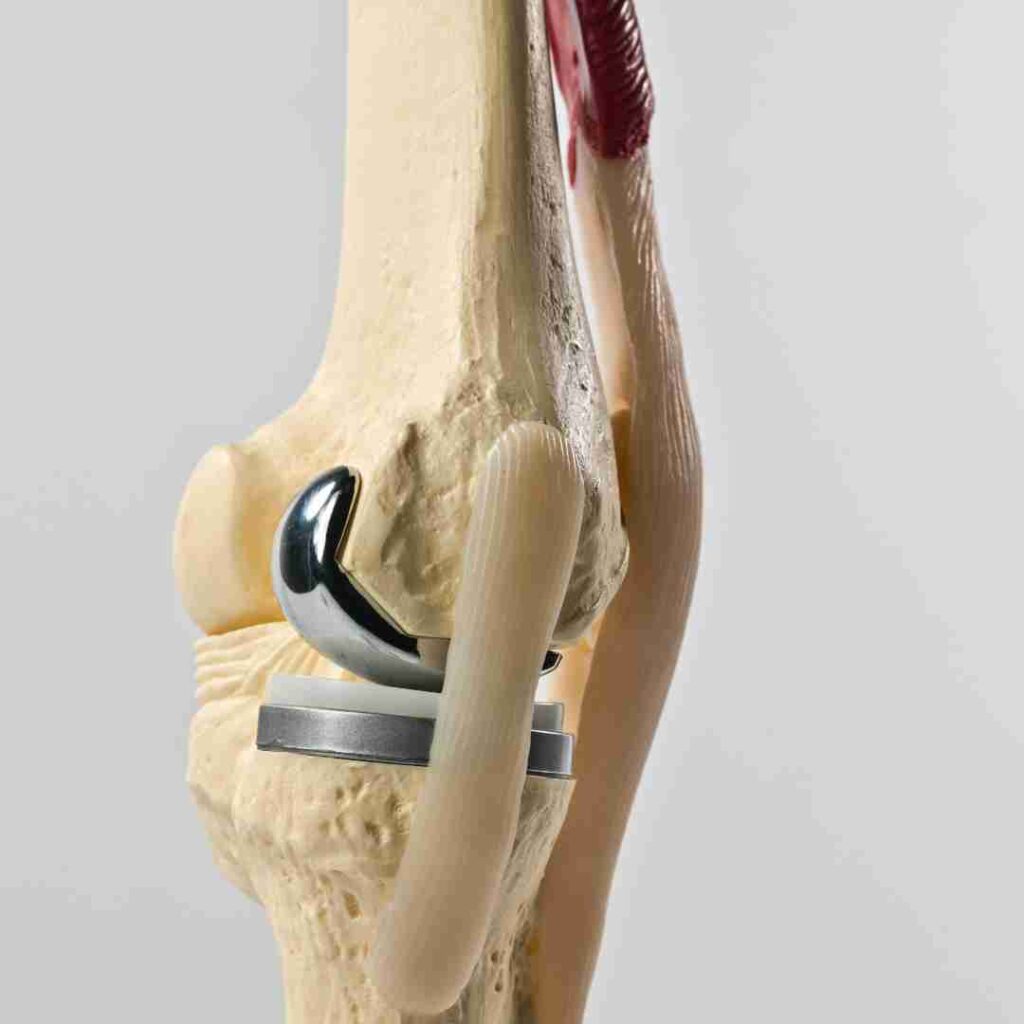

Knee revision surgery is a specialized procedure done to correct problems after a previous knee replacement, such as implant loosening, wear, infection, instability, or ongoing pain. In Hyderabad, this surgery involves detailed imaging, careful surgical planning, and advanced orthopedic techniques to remove or replace damaged implants and restore proper knee alignment, strength, and movement. The treatment is customized based on the condition of the existing implant, bone quality, patient age, activity level, and overall health, to improve function, reduce pain, and help patients return to daily life safely.

Knee revision surgery in Hyderabad is designed to treat problems that can occur after a previous knee replacement, such as implant wear, loosening, infection, or persistent pain. The procedure focuses on carefully assessing the existing implant, restoring proper alignment and stability, and improving knee movement using advanced imaging and proven surgical techniques. Since every case is different, treatment is customized based on bone condition, implant status, patient age, activity level, and overall health—helping patients regain confidence, mobility, and a better quality of life.

Knee revision surgery is usually needed when a previous knee replacement develops problems like implant loosening, wear, infection, or bone loss. A careful evaluation by an experienced orthopedic surgeon helps determine the right treatment approach to restore knee stability, function, and comfort.